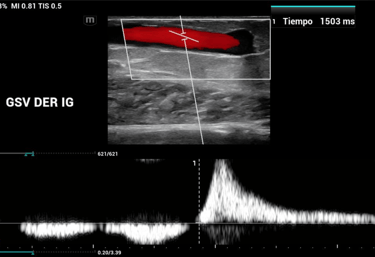

Endovascular

Intervenciones mínimamente invasivas para salud vascular óptima.